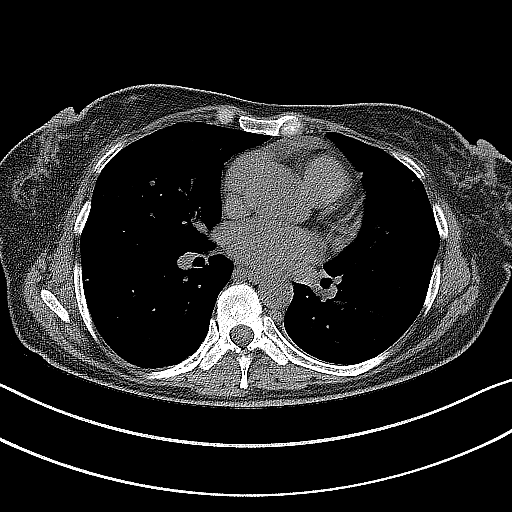

Reconstructed NATIVE CT scan (cycle consistency)

Full window (WL 1023.5, WW 4095 β†’ Low βˆ’1024, High +3071)

Actual HU range: [-1024.0, 1627.2]

Lung window (WL -600, WW 1500 β†’ Low βˆ’1350, High +150)

Actual HU range: [-1120.3, 150.0]

Mediastinum window (WL 40, WW 400 β†’ Low βˆ’160, High +240)

Actual HU range: [-160.0, 240.0]